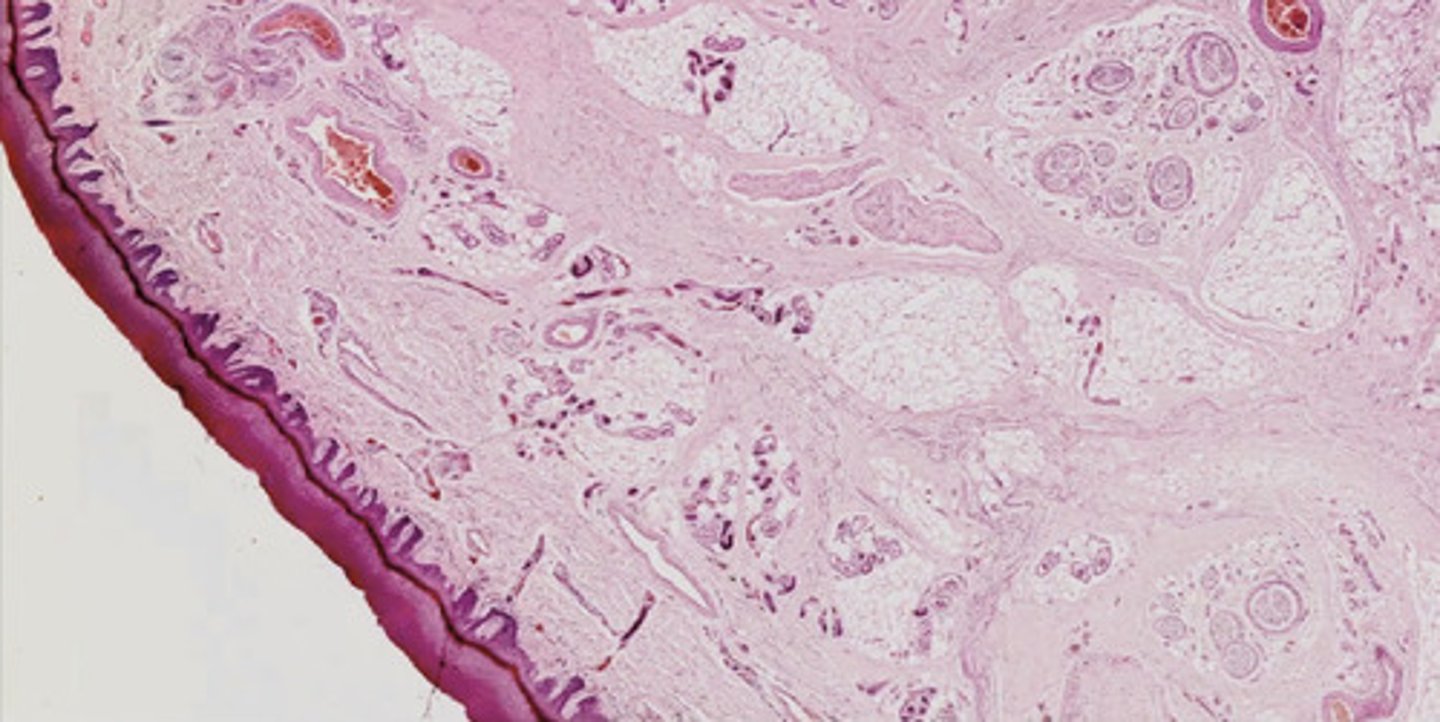

Warga ustna - przekrój strzałkowy (H+E)